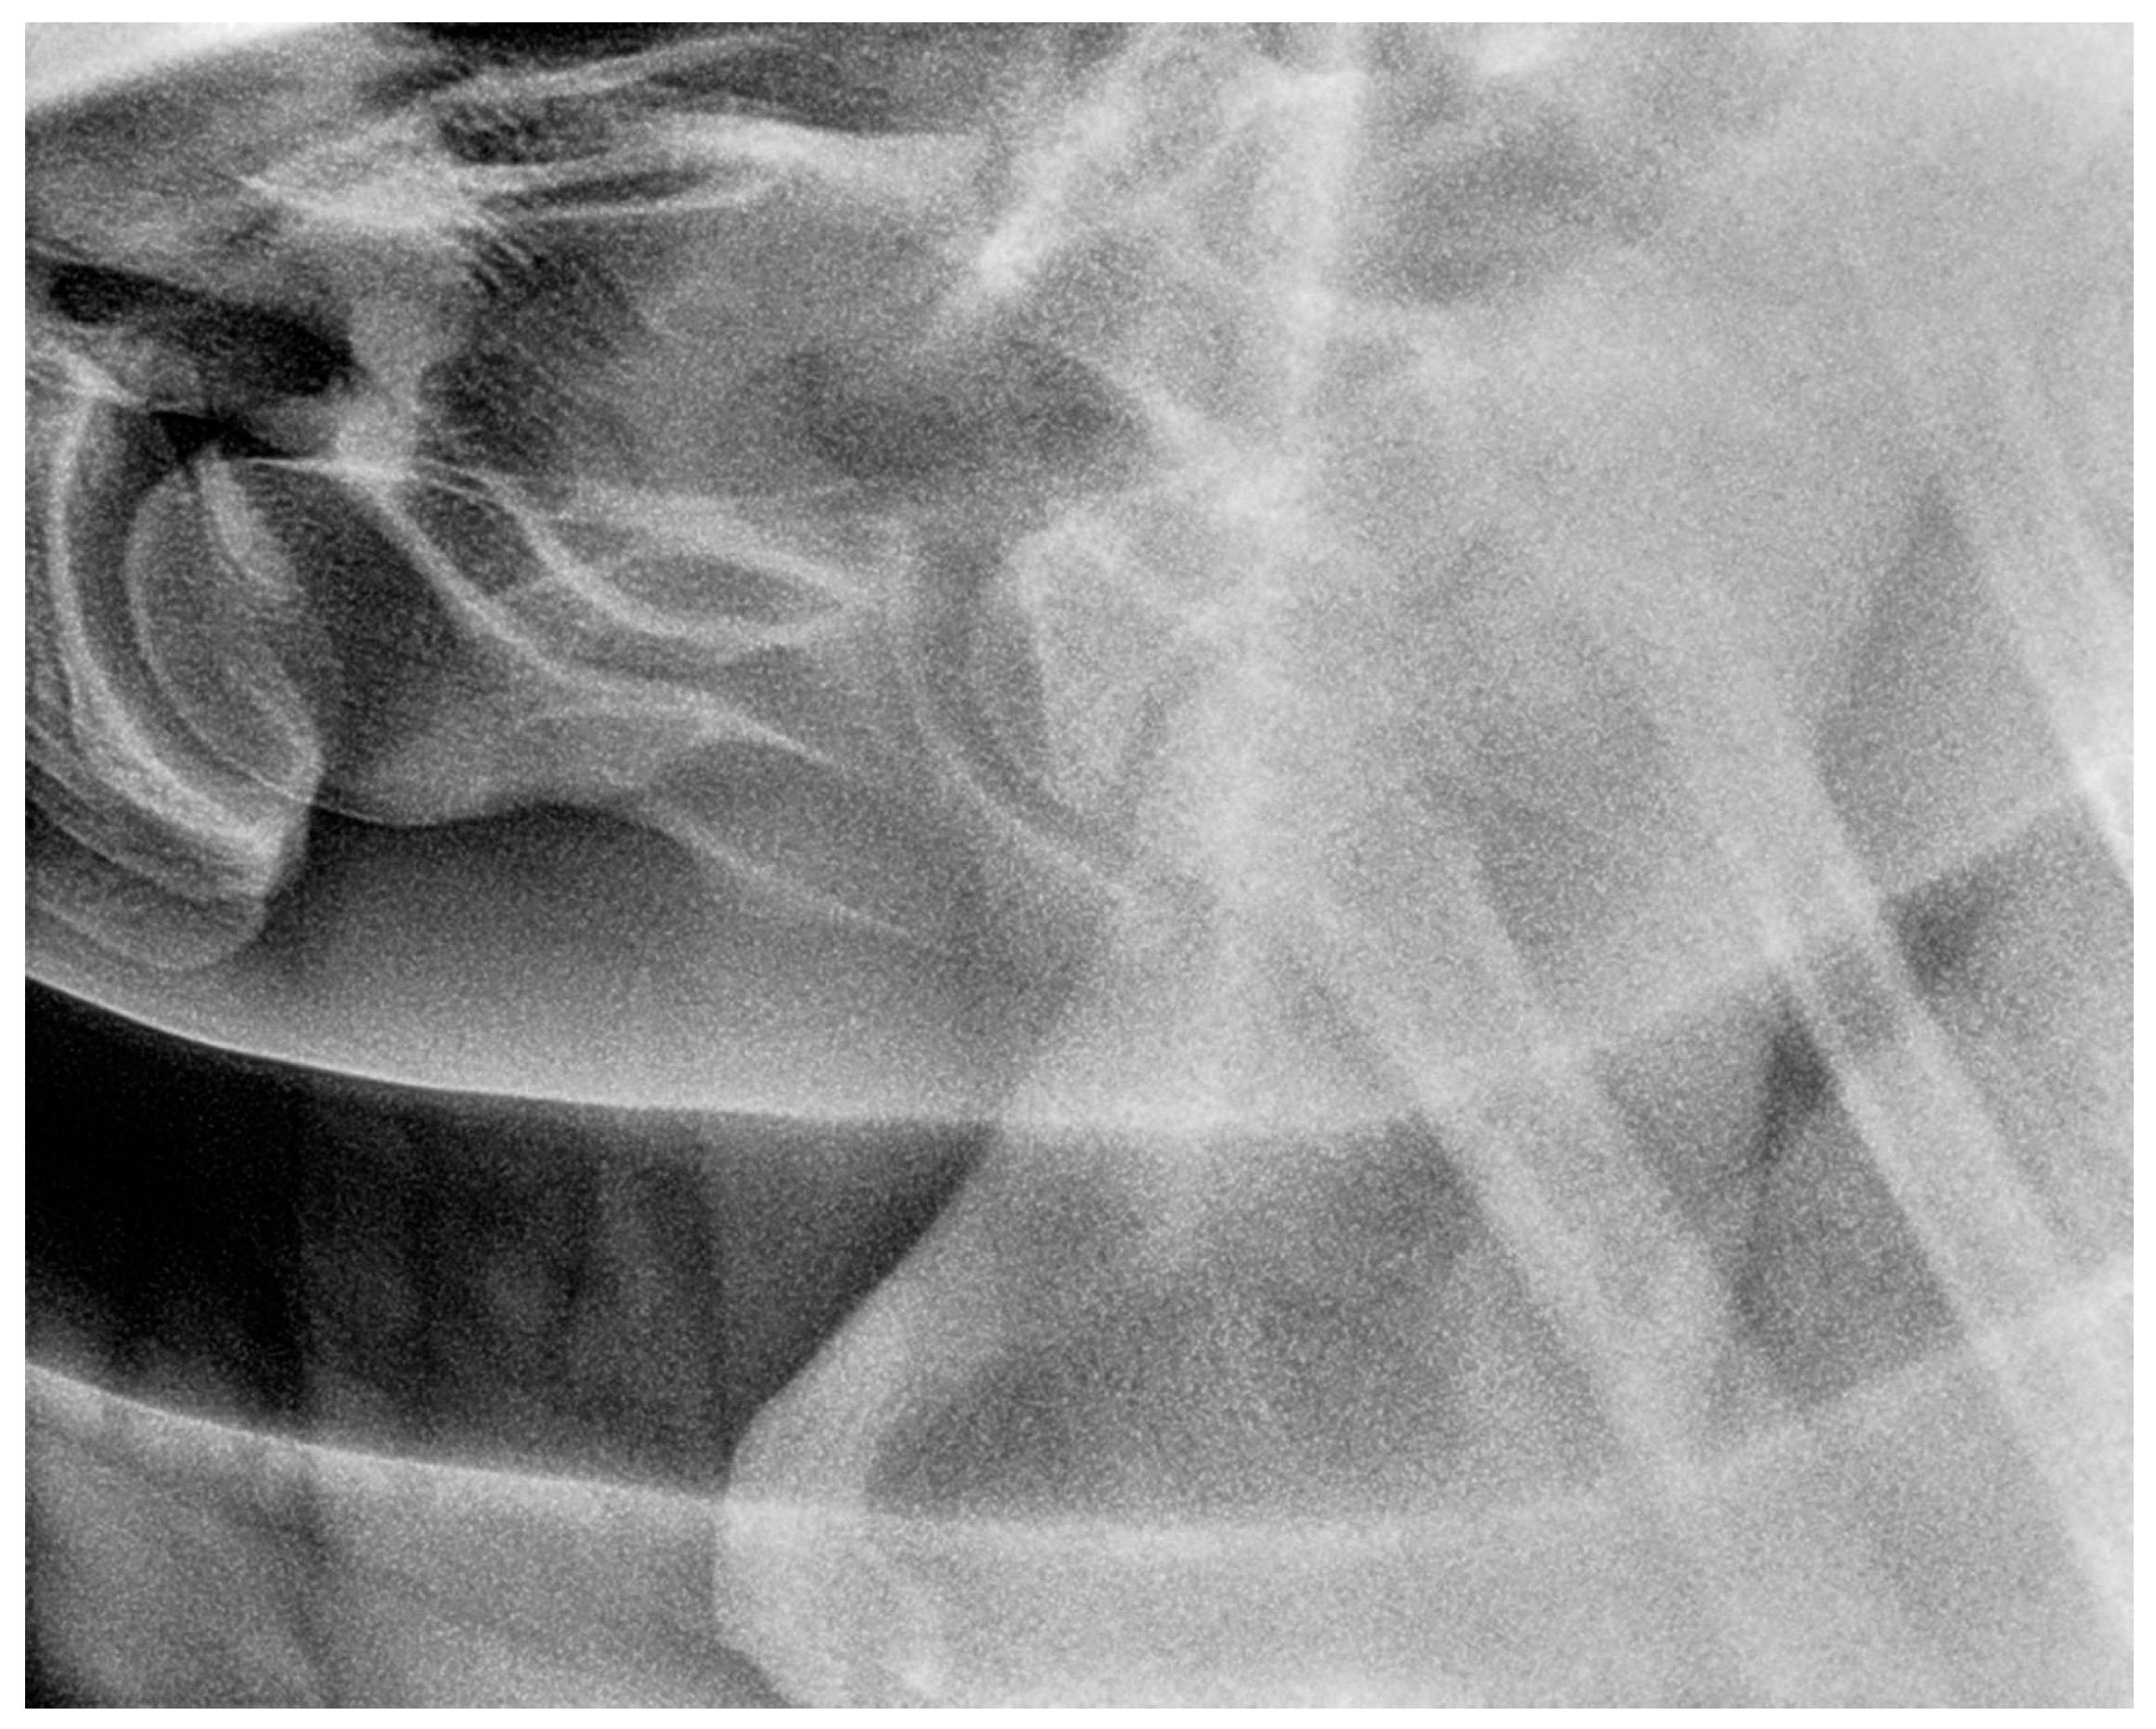

2.3. Radiographic Method

2.4. Classification System